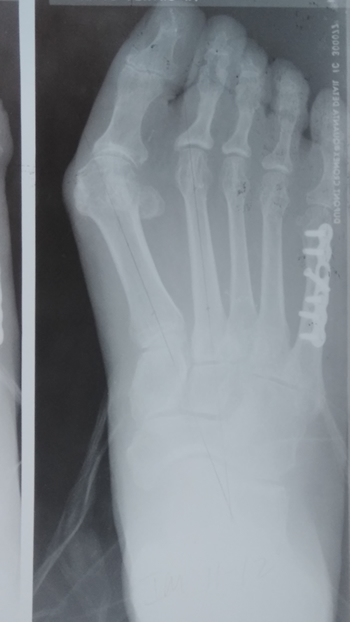

5th digital surgery

Pre & Post-op. Bunion and 5th Digital Surgery

Post-op